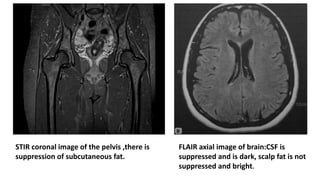

STIR( Short Tau Inversion Recovery)

• Used to suppress the signal from fat

• When 90 degree pulse is applied at short TI, LM for all tissues are still

on negative side. The tissues short T1,Ex- Fat have near zero

magnetization, so don’t have much signal.

• Most pathological tissues have increased T1 as well as T2.

• Moderately high TE used in STIR allows tissues with high T2 to retain

signal while tissues with short T2 will reduced signal.

• This results in increased contrast between tissues with short T1 –T2

and long T1-T2

** Most pathology appeared bright on STIR making them easier to pick

up

FLAIR (Fluid Attenuated Inversion Recovery)

• Used to suppress the signal from fluid.

• When 90 degree pulse is applied at long TI, LM of most tissues is

almost fully recovered.

• Since water has long T1 its LM recovery is at half way stage at long TI.

This results in no signal from fluid such as CSF.

• As in STIR most of the pathologies appeared bright on FLAIR

• In FLAIR long TE can be used to get heavily T2 weighted image

without problems from CSF partial volume effects

STIR coronal image of the pelvis ,there is

suppression of subcutaneous fat.

FLAIR axial image of brain:CSF is

suppressed and is dark, scalp fat is not

suppressed and bright.